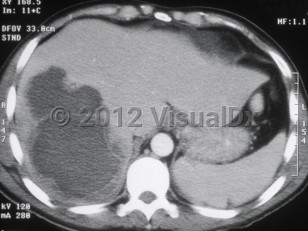

Amebic liver abscess

Laboratory evaluation reveals leukocytosis, elevated transaminases, and elevated alkaline phosphatase. The abscess can be visualized by computed tomography or ultrasound. Usually only one lesion is seen. Most of the time, the lesion is located in the right lobe of the liver.